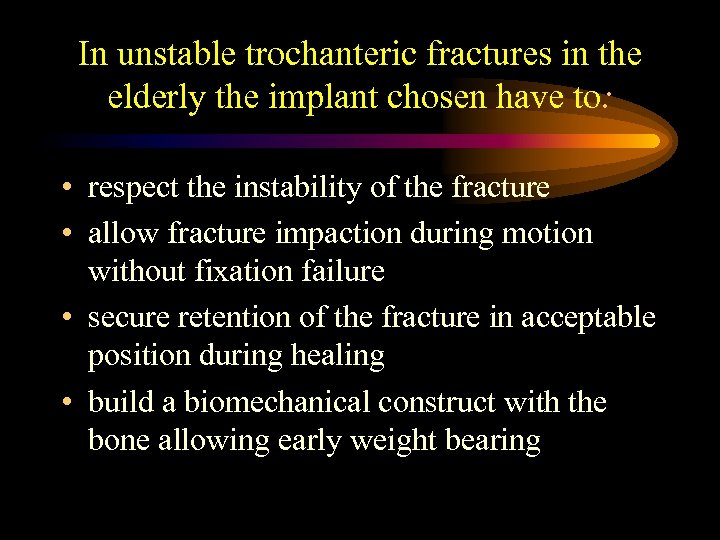

In unstable trochanteric fractures in the elderly the implant chosen have to: • respect the instability of the fracture • allow fracture impaction during motion without fixation failure • secure retention of the fracture in acceptable position during healing • build a biomechanical construct with the bone allowing early weight bearing

In unstable trochanteric fractures in the elderly the implant chosen have to: • respect the instability of the fracture • allow fracture impaction during motion without fixation failure • secure retention of the fracture in acceptable position during healing • build a biomechanical construct with the bone allowing early weight bearing